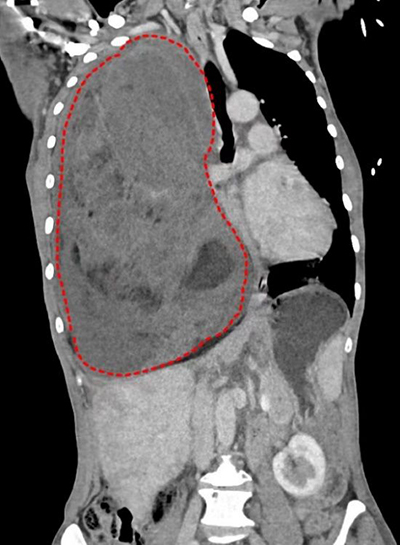

入院CT报告提示:右侧胸腔可见巨大混杂密度肿块,大小约为30*17*17cm。(红色虚线标记范围为巨大胸腔肿瘤)

经过多方打听,玛合帕丽了解到省立医院刘相燕主任医师团队在复杂纵隔肿瘤的手术治疗方面有着丰富的经验。此前,刘相燕主任已完成多例复杂纵隔肿瘤的外科治疗,但肿瘤生长到如此体积确实罕见:患者胸部CT显示肿瘤长径达30厘米,完全占据右侧胸腔,心脏也被挤压到了一旁。患者既往病理诊断为脂肪肉瘤,经过两个周期的化疗,肿瘤体积不降反增。胸腔巨大恶性肿瘤且对化疗不敏感,日渐增长的肿瘤导致患者病情继续恶化,随时可能有生命危险,手术切除成为当前治疗的唯一方法。与此同时,手术存在巨大的风险:肿瘤体积巨大导致手术操作空间极小、肿瘤血供丰富且侵袭性强,稍有不慎会导致不可控制的大出血、肿瘤长期压迫导致心脏移位,一旦肿瘤切除可能会影响血液循环稳定甚至心跳骤停……一系列的风险对手术团队提出了巨大挑战。但患者面对疾病的痛苦和绝望,以及家属对团队的无条件信任,让刘相燕主任医师团队下定决心挽救这个濒临破碎的家庭。